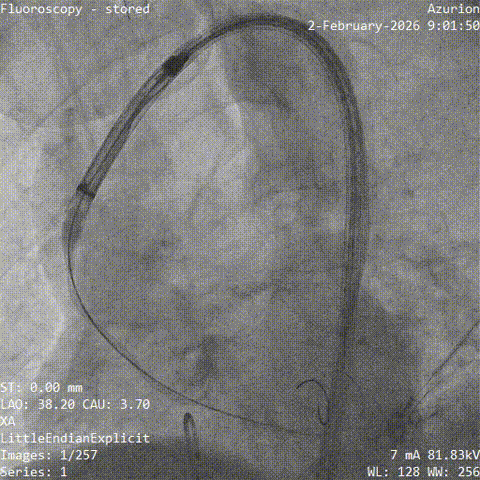

▲导丝跨瓣

▲18mm球囊预扩

▲输送器过弓

▲瓣膜定位

▲释放至工作位

▲工作位造影

▲脱钩

▲20mm球囊后扩

▲最终造影

手术当天,团队顺利完成经导管主动脉瓣置换术。术中瓣膜释放位置理想,人工瓣膜功能良好,未见明显瓣周漏,也未出现严重传导阻滞、恶性心律失常等情况,患者术后安返CCU病房。